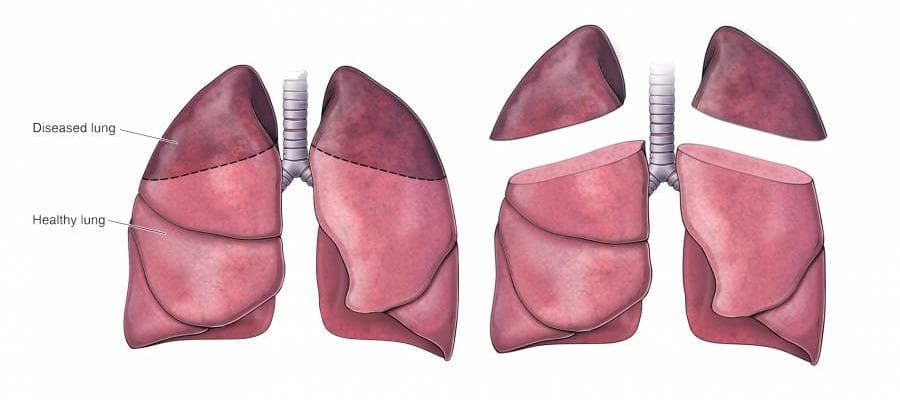

Lung volume reduction surgery (LVRS) is a specialized surgical procedure aimed at improving the quality of life and breathing efficiency in patients suffering from severe emphysema, a type of chronic obstructive pulmonary disease (COPD). Emphysema is characterized by the destruction of the air sacs in the lungs (alveoli), leading to large, ineffective spaces that reduce lung function and cause significant breathing difficulties. LVRS works by removing these diseased portions of the lung, typically around 20% to 35% of the lung tissue, to allow the remaining, healthier tissue to function more effectively.

The surgery involves removing the most damaged parts of the lungs, typically the upper lobes, to allow the remaining healthier lung tissue to function more effectively. This can enhance lung elasticity, reduce shortness of breath, and improve the patient's ability to exercise.